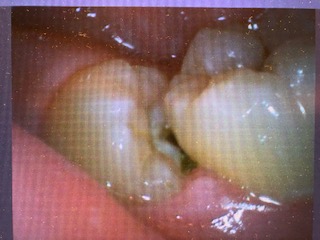

・中途半端に生えていて、歯ぐきが炎症を起こしやすい場合

基本的に親知らずは変な方向や位置に生えてくることが多いので、歯と歯の間に食べかすが詰まりやすく歯ぐきが炎症を起こしやすいです。

何回も炎症を繰り返すことで段々悪化し、腫れや痛みが短いサイクルで訪れひどくなっていきます。